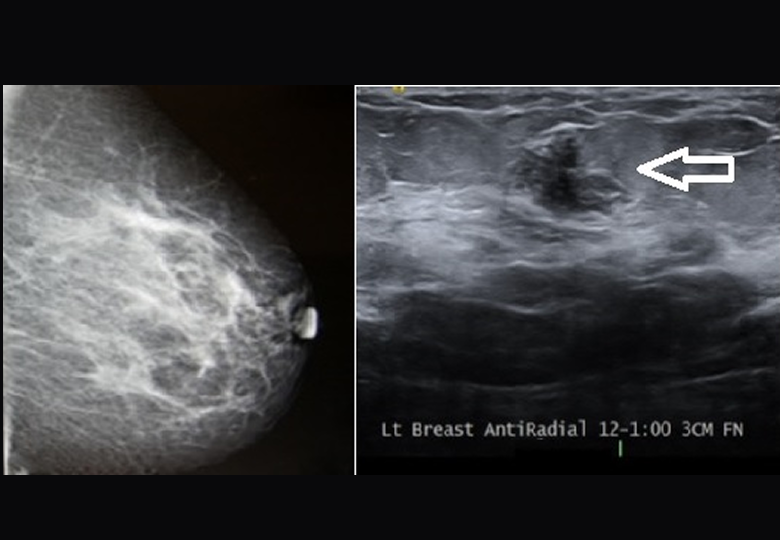

Over 40,000 women die each year from breast cancer in the United States alone. Many cancers go undetected through traditional mammograms, especially in patients with dense breast tissue. While ultrasound can double the detection rate, challenges like breast deformability and operator dependency often compromise scan quality—leading to missed sub-centimeter cancers.

MetriTrack is dedicated to advancing automated breast ultrasound solutions that aim to detect more cancers, faster and at a lower cost. With support from ASSIST Software, MetriTrack enhanced its technology by replacing manual probe position estimation with high-precision dynamic mapping, improving accuracy and consistency in breast imaging.